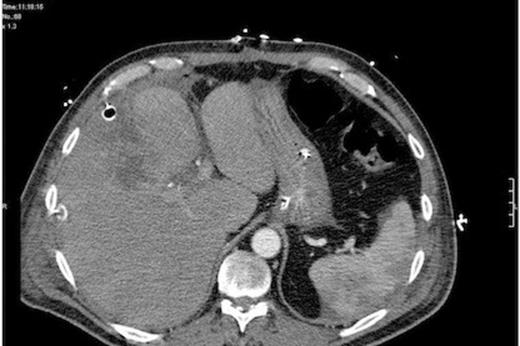

Initial treatment comprised intravenous fluid resuscitation, high flow oxygen and broad spectrum antibiotics (Tazocin, Gentamicin and Metronidazole). He proceeded to CT scan which demonstrated a gas filled cavity in and under the right lobe of liver. A laparotomy was performed, revealing a large abscess cavity in the right lobe of liver emanating from the gallbladder fossa. This contained pockets of gas. The bile duct was found intact and the cystic duct clips secure. The pus was drained and a generous peritoneal lavage performed. Large bore (32Fr) sub-hepatic and sub-phrenic drains were placed.

CT at re-admission 1 week post lap chole - Free intraperitoneal gas abscess in gallbladder fossa